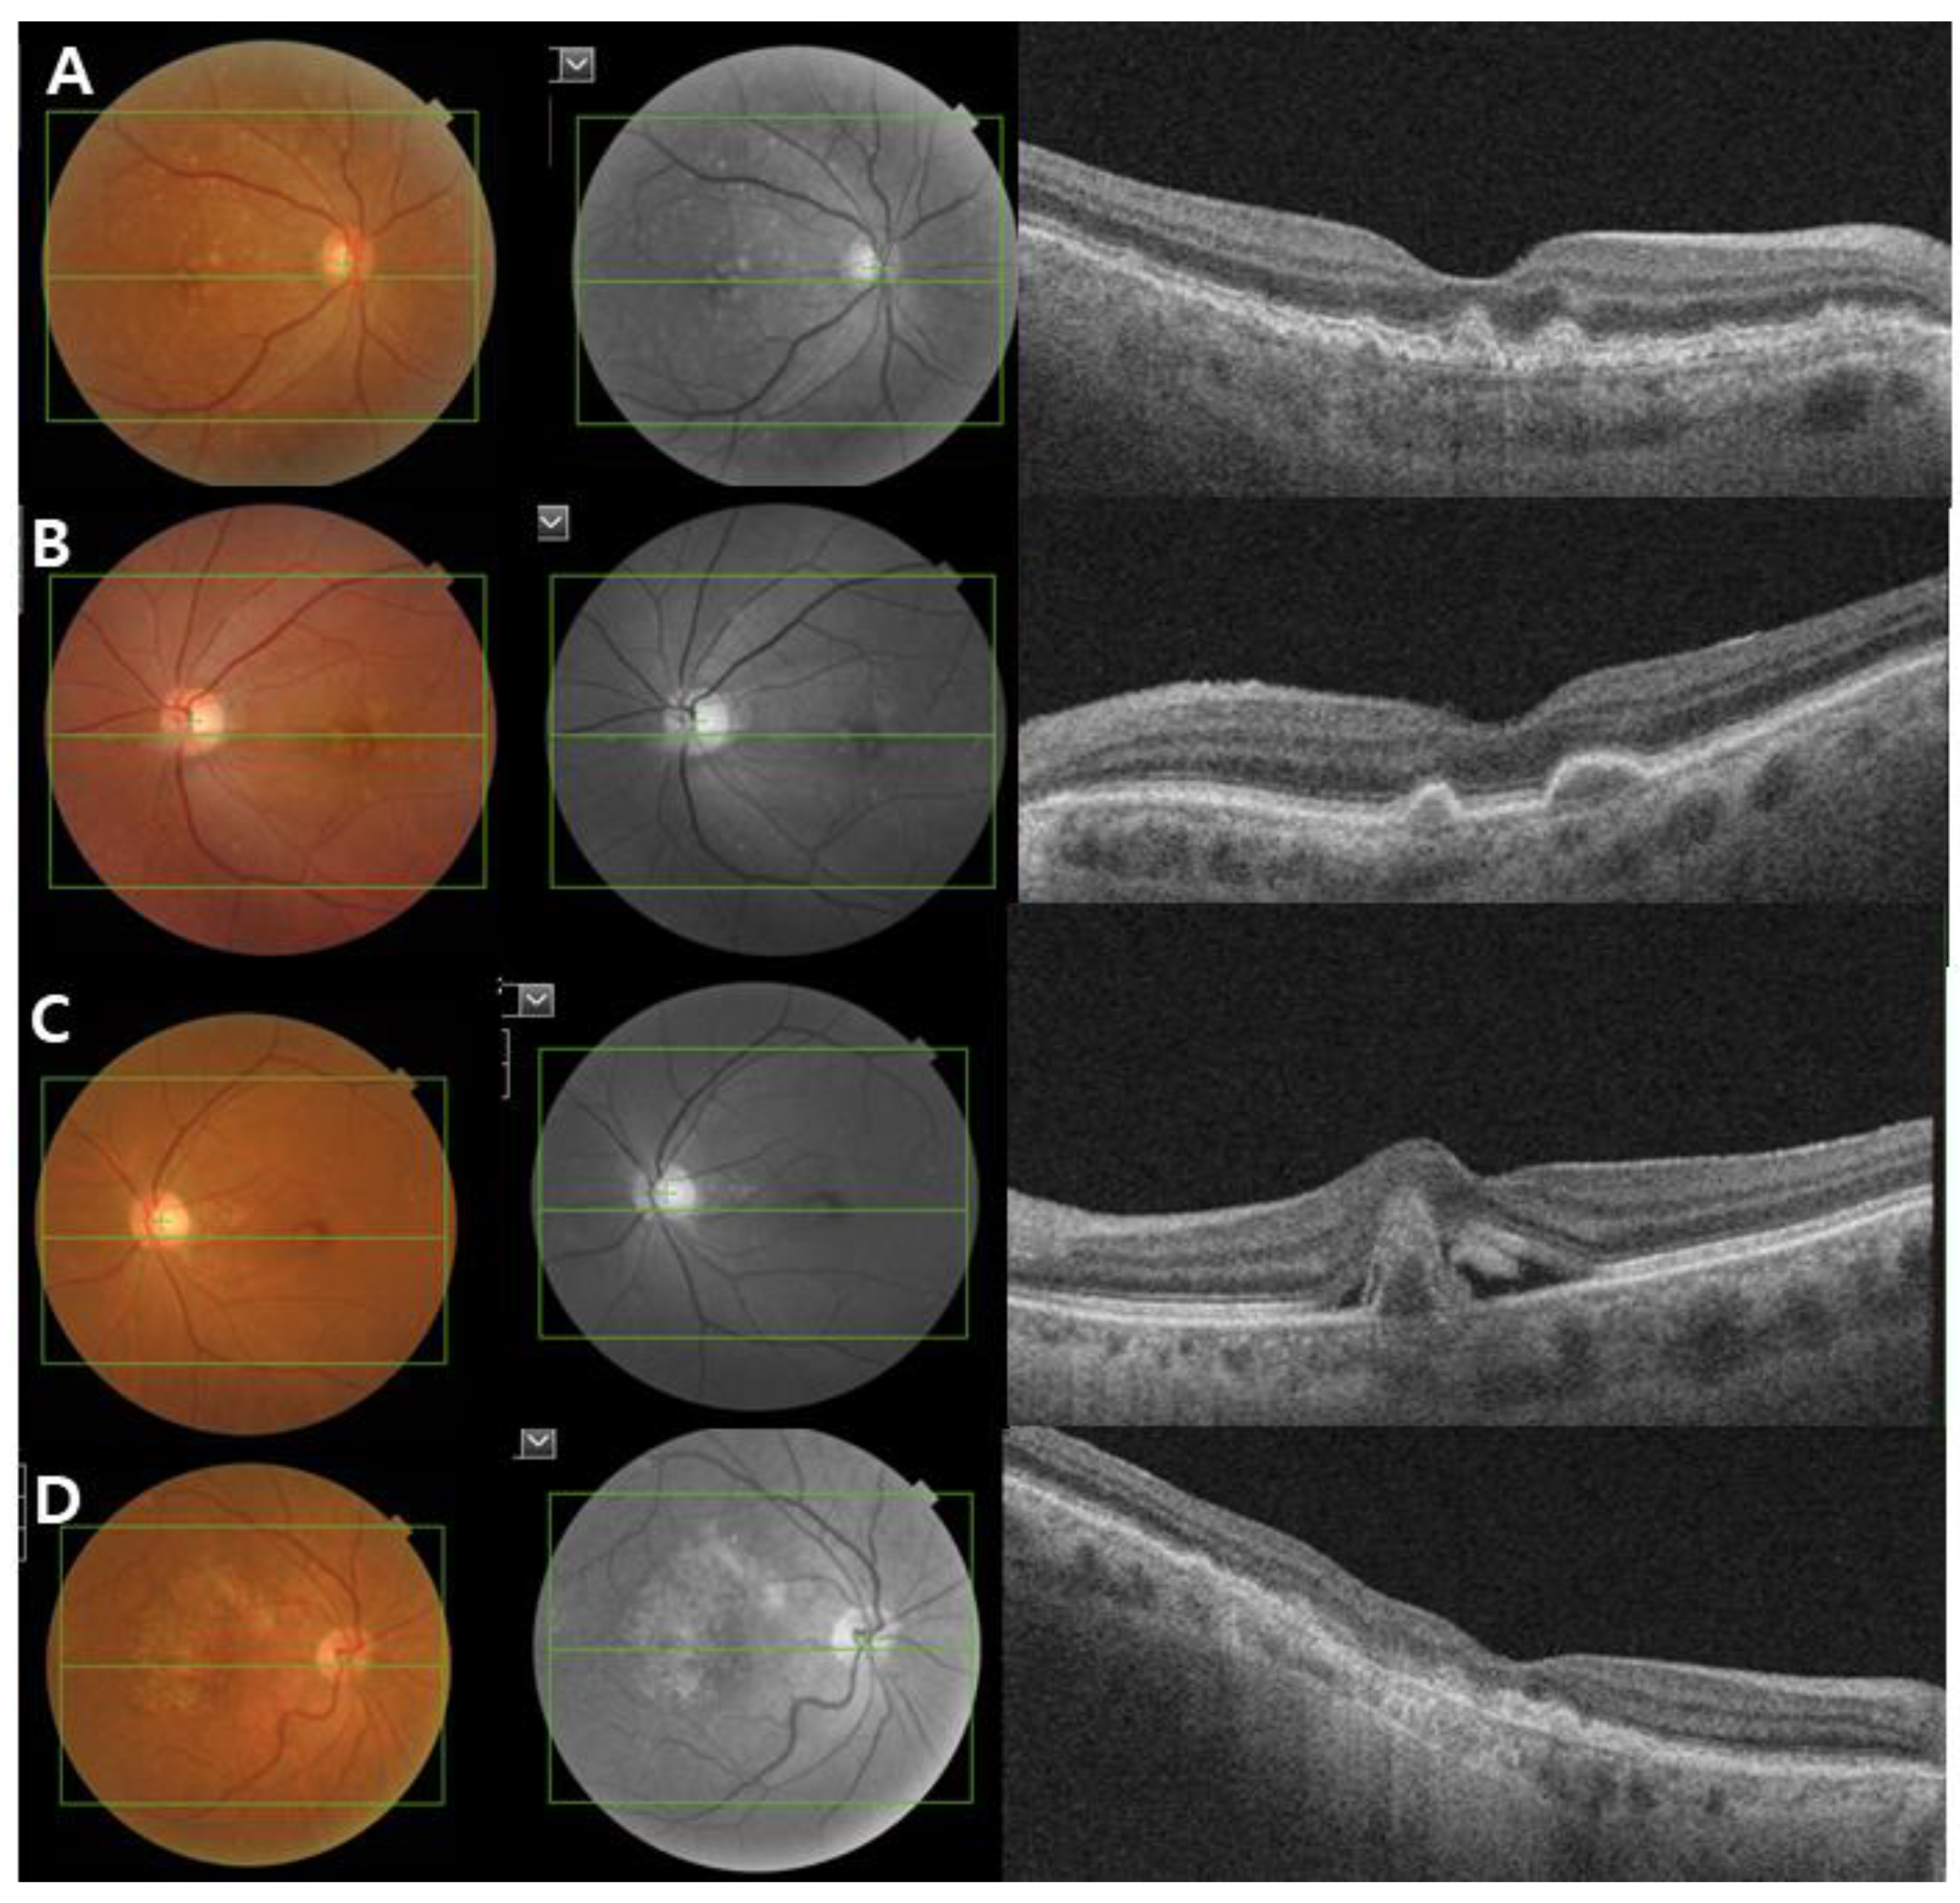

2. Clinical Classification of AMD

| AMD Classification | Definition |

|---|---|

| No AMD | No drusen and no AMD pigmentary changes |

| Normal aging changes | Small drusen (≤63 µm) and no AMD pigmentary abnormalities * |

| Early AMD | Medium sized drusen (>63 µm and ≤125 µm) and no pigmentary changes |

| Intermediate AMD | Large sized drusen (>125 µm) and/or pigmentary changes |

| Late AMD | Neovascular AMD or geographic atrophy |